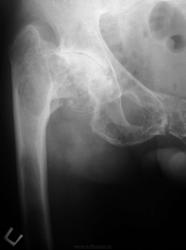

Может быть фиброзная остеодисплазия полиоссальная форма?

Была подборка на сайте по болезни Олье.

Я бы в первую очередь подумала о фиброзной дисплазии. Нельзя исключить гиперпаратиреоидную дистрофию.